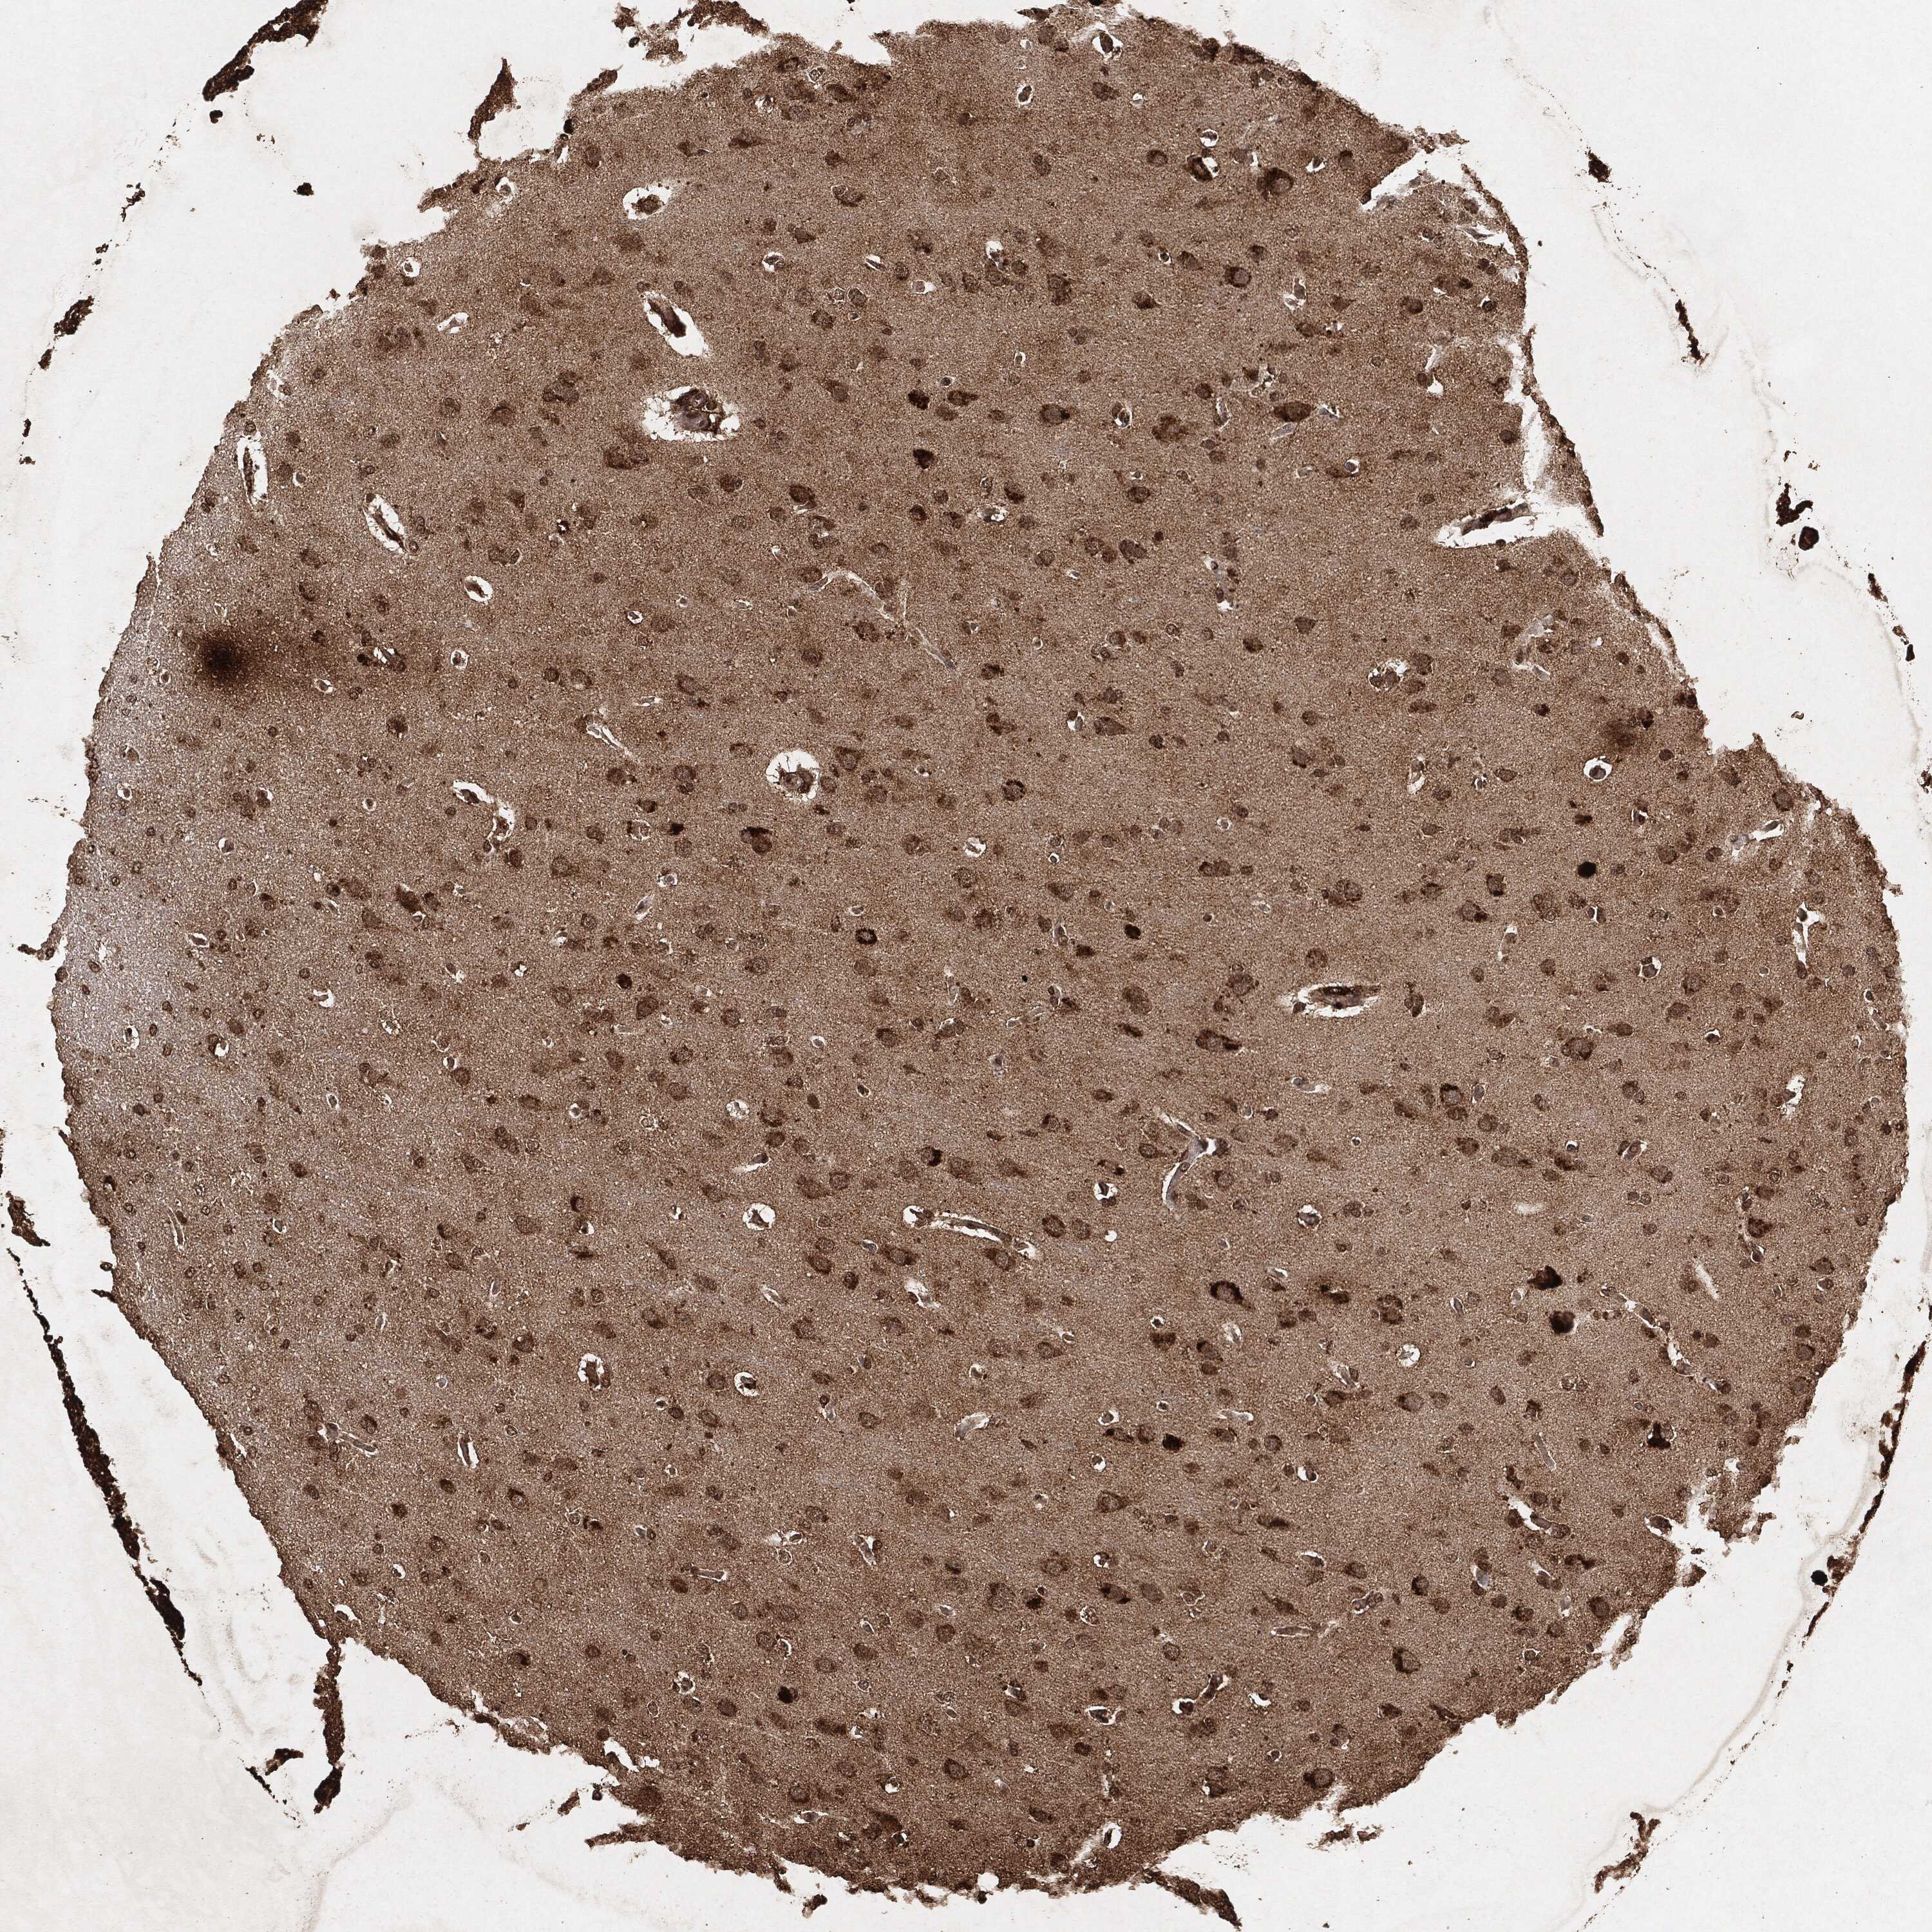

GLIOMA - Protein expressioni

A mouse-over function shows sample information and annotation data. Click on an image to view it in a full screen mode. Samples can be filtered based on level of antibody staining by selecting one or several of the following categories: high, medium, low and not detected. The assay and annotation is described here.

Note that samples used for immunohistochemistry by the Human Protein Atlas do not correspond to samples in the TCGA dataset.

Antibody stainingi

Antibody staining in the annotated cell types in the current human tissue is reported as not detected, low, medium, or high, based on conventional immunohistochemistry profiling in selected tissues. This score is based on the combination of the staining intensity and fraction of stained cells.

Each image is clickable and will lead to virtual microscopy that enables deeper exploration of all samples and also displays staining intensity scores, fraction scores and subcellular localization as well as patient and tissue information for each sample.

Glioma, malignant, High grade

Glioma, malignant, Low grade

Glioma, malignant, NOS